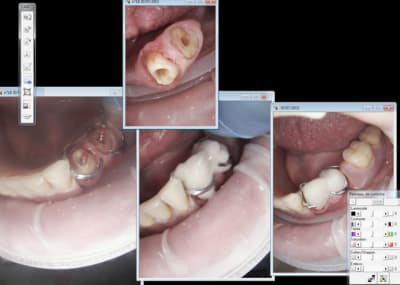

chicot29

1 .Essayage cones en place, couper ce qui dépasse le cas échéant ( une sur instrumentation ca arrive)

2. scellement des cones.

3. couper les cones au friendo puis phase de descente au friendo ( qui est un heater plugger je le rappelle) et compactage au machtou.

4. coincer les chutes de gutta à l' entrée des canaux et les thermo-compacter au mac spadden.

C'est pret ! -))))

Par contre j'ai essayé le clip flow pour protéger l'entrée des canaux lors de la réalisation pré endo ( endo en 2 temps because urgence) autant ca marche bien pour les onlays autant c'est la galère à virer dans ce cas. -)))))

C'est à moitié mou le r25 passe à travers heureusement ! -))))